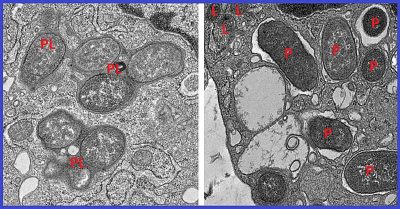

Malattia di Crohn-immagine: le micrografie elettroniche mostrano come i macrofagi che esprimono la girdina neutralizzino i patogeni fondendo i fagosomi (P) con i lisosomi cellulari (L) per formare i fagolisosomi (PL), compartimenti in cui i patogeni e i detriti cellulari vengono degradati (sinistra). Questo processo è cruciale per il mantenimento dell’omeostasi cellulare. In assenza di girdina, questa fusione fallisce, consentendo ai patogeni di eludere la degradazione e la neutralizzazione (destra). Credito: UC San Diego Health Sciences.

I ricercatori hanno poi confermato l’importanza dell’interazione tra NOD2 e girdina confrontando modelli murini di morbo di Crohn privi della proteina girdina con quelli con girdina intatta. Hanno scoperto che i topi privi di girdina soffrivano di uno squilibrio nel microbioma intestinale e sviluppavano un’infiammazione dell’intestino tenue. Spesso morivano di sepsi, una condizione in cui il sistema immunitario innesca una risposta eccessiva a un’infezione, causando infiammazione in tutto il corpo e danni agli organi vitali.